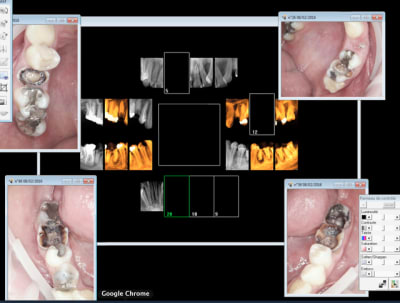

Miracle la 26 était vivante. -))))

Pas facile de trouver les 4 canaux c'est le Mv1 qui a été le plus dur une fois n'est pas coutume ! -)))

Le reste va dégager chez le stomato. J'ai viré la 24 en en chiant assez comme ca après l'endo de 26. Chacun doit faire sa B.A. -)))

J'ai juste la place de faire une ceram sur 26 une fois que 36 sera enlevée. -))))

> Miracle la 26 était vivante. -))))

>

> Pas facile de trouver les 4 canaux c'est le Mv1 qui a été le plus dur une fois

> n'est pas coutume ! -)))

>

> Le reste va dégager chez le stomato. J'ai viré la 24 en en chiant assez comme ca

> après l'endo de 26. Chacun doit faire sa B.A. -)))

>

> J'ai juste la place de faire une ceram sur 26 une fois que 36 sera enlevée.

> -))))

Tu travailles sous microscope électronique?

ca coute combien (à financer et à honorer par le patient)?

Ah ouai j'avais pas bien regardé les photos. Comment as-tu trouvé MV1, parce que sur la photo en haut à droite on ne le voit pas du tout.

Le feeling et un bon sx protaper. -)))

Et pour les photos c'est un microscope ou c'est une caméra endobuccale?

C'est vrai ma reconstitution préendo était bien collée à l'entrée du MV1 dommage que le patient consultait à cause de douleurs. Il serait venu 15 jours avant ca aurait pu le faire. -)